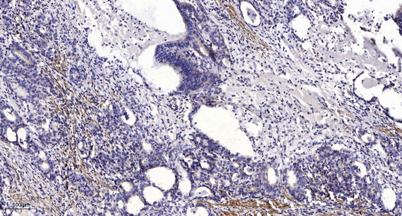

Immunohistochemical analysis of paraffin-embedded human Gastric adenocarcinoma. 1, Antibody was diluted at 1:200(4° overnight). 2, Tris-EDTA,pH9.0 was used for antigen retrieval. 3,Secondary antibody was diluted at 1:200(room temperature, 45min).